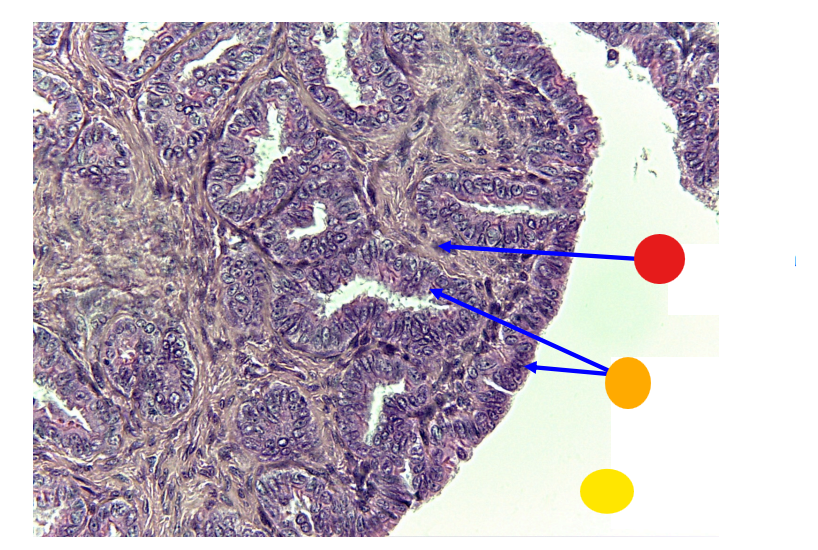

red

granulosa cells

orange

primary oocyte

what is this

primary follicle

red

granulosa cells

orange

thecal cells

yellow

zona pellucida

What is this

secondary follicle